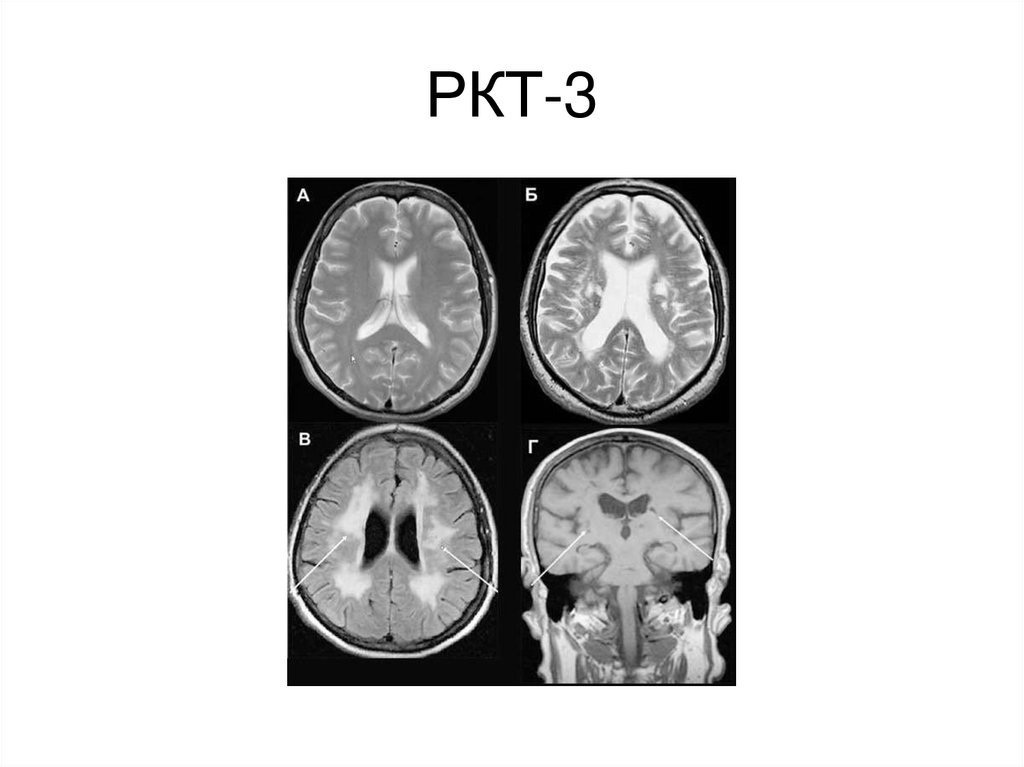

РКТ-3

69. РКТ-3